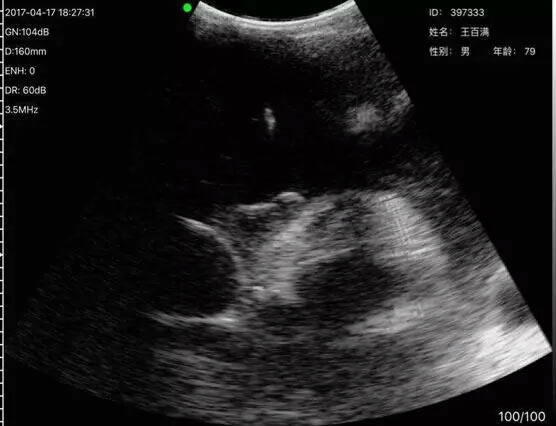

索诺星掌超再次来到三明市,今天参加了夏茂镇在后垅村举行的体检活动,受到了医生和村民们的高度评价,掌超助力基层诊疗能力提升,让更多人更方便

索诺星掌超再次来到三明市,今天参加了夏茂镇在后垅村举行的体检活动,受到了医生和村民们的高度评价,掌超助力基层诊疗能力提升,让更多人更方便更低成本获得好的医疗服务VIEW MORE →2023-03-02 -